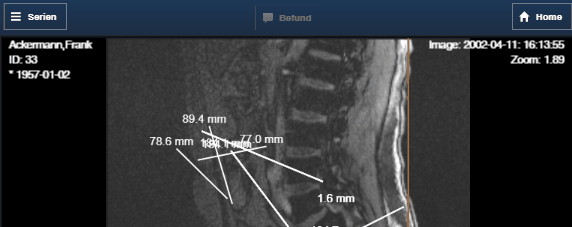

Ecktexte bei Mouse/Touch Operation ignorieren. Mousaktionen (Fensterung, Stacken, Zoomen ...) können jetzt auch über den Ecktexten ausgeführt werden, was besonders auf mobilen Geräten zu Problemen geführt hat.